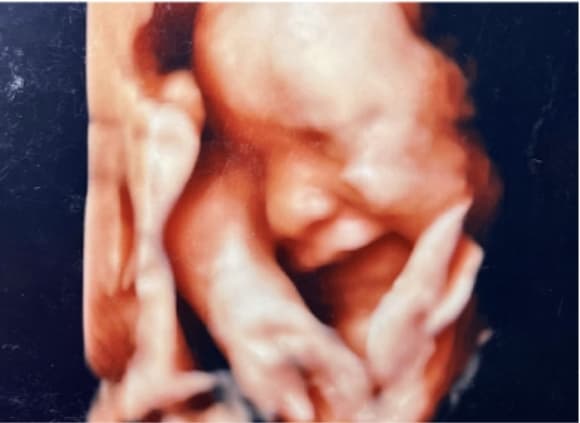

4Dエコー外来

• 妊婦健診の中でいつでもご希望の時に、お腹の中の赤ちゃんの状態を立体的に、そして動きまでリアルにご覧いただける超音波技術を用いた4Dエコー外来が受診できます。

• お腹の中のお子さまの様子を鮮明にご覧いただくことが可能です。(希望者のみ:2,160円/回)

※当日の胎児の向きや、姿勢によって必ずしも顔がはっきり見られるとは限らないため、費用は見えたときのみいただいております。

4D胎児エコー写真

(10週)

(12週)

(30週)

(36週)